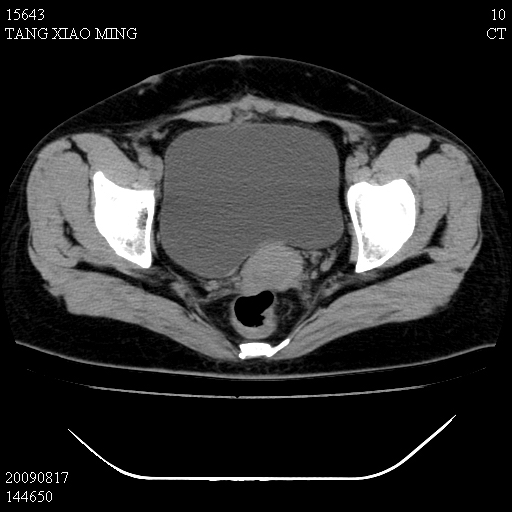

标题: CT21692:盆腔病变

女,33岁,右下腹痛2年余,既往宫外孕病史,如在我院手术,结果下周公布,

可能的诊断。1子宫内膜异位【子宫腺肌症并右卵巢巧克力囊肿】;2 右卵巢囊腺瘤。子宫肌瘤

1)考虑卵巢巧克力囊肿,不排除卵巢囊腺瘤。2)子宫肌瘤可能。

卵巢囊腺瘤,子宫肌瘤,直肠壁厚,不除外占位.